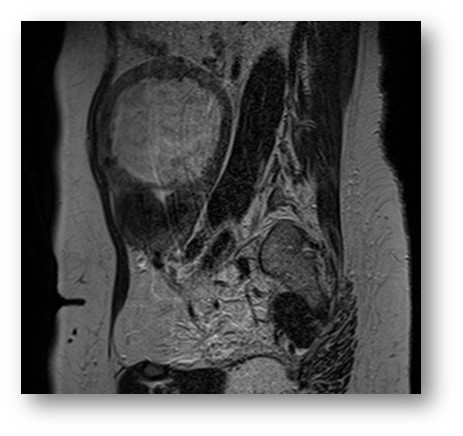

КТ диагностика тубоовариального абсцесса: Подходы и изображения

Раздел: Объективный взгляд